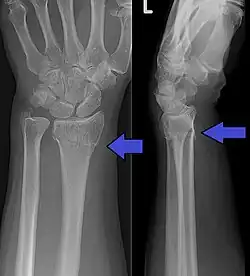

Malreduced distal radius fracture demonstrating the deformity in the wrist

Dorsal displacement of carpal bones seen in dorsally angulated distal radius fracture, creating a fork-like appearance

"Dinner fork" deformity

Swelling, deformity, tenderness, and loss of wrist motion are normal features on examination of a person with a distal radius fracture. "Dinner fork" deformity of the wrist is caused by dorsal displacement of the carpal bones (Colle's fracture). Reverse deformity is seen in volar angulation (Smith's fracture). The wrist may be radially deviated due to shortening of the radius bone.[5] Examination should also rule out a skin wound which might suggest an open fracture, usually at the side.[5] Tenderness at an area with no obvious deformity may still point to underlying fractures. Decreased sensation especially at the tips of the radial three and one half digits ( thumb, index finger, middle finger and radial portion of the ring finger ) can be due to median nerve injury. Swelling and displacement can cause compression on the median nerve which results in acute carpal tunnel syndrome and requires prompt treatment. Very rarely, pressure on the muscle components of the hand or forearm is sufficient to create a compartment syndrome which can manifest as severe pain and sensory deficits in the hand.[5]